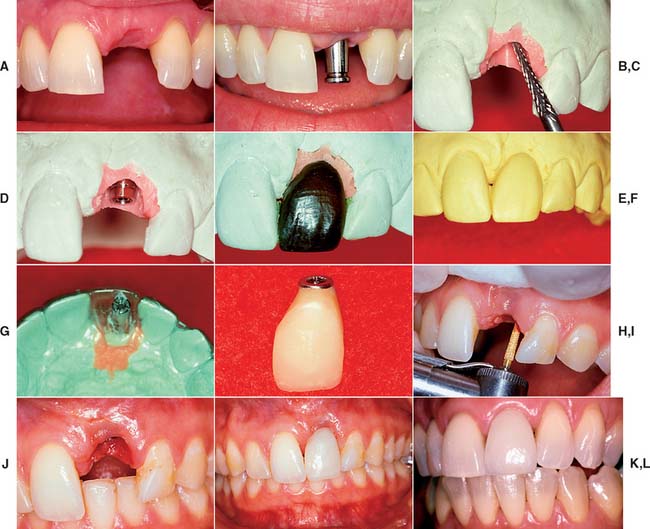

Matching the soft tissue contours of adjacent natural teeth remains the most difficult challenge for completing the anterior single-tooth restoration. These contours can be reliably created with interim restorations. One technique, which combines soft tissue contouring and interim placement, is shown in Figure 13-45. When the tissue has matured around the interim restoration, a final impression can be made to complete the definitive restoration (Fig. 13-46). Impressions can also be made at the time of stage I surgery so that an interim restoration can be delivered at stage II to facilitate more ideal soft tissue contours (Fig. 13-47). The best soft tissue esthetics is still generally achieved when interdental papillae are present before the surgery. If soft tissue contours are deficient before surgery, the patient should expect some compromise in the final soft tissue result.

Fig. 13-45 Soft tissue contouring with interim restoration. A, This patient has lost the left maxillary central incisor, which will be replaced with an implant-supported prosthesis. B, Soft tissue healing 2 weeks after second-stage surgery and placement of an impression coping. Note that the interdental papilla has been preserved. C, Soft tissue cast prepared with a laboratory bur to create the ideal soft tissue architecture. D, A waxing sleeve attached to the implant analog retains the interim restoration. E, An anatomic-contour wax pattern can be used to fabricate the interim restoration. F, Duplicate cast of the anatomic-contour wax pattern. G, An acrylic template is adapted to the duplicate cast and returned to the definitive cast. A waxing post is placed in the interim restoration to create a screw access hole. H, An interim implant-supported restoration is fabricated by one of the techniques described in Chapter 15. I, The soft tissue is contoured to accept the interim restoration. A diamond curettage bur can be used when sufficient attached tissue is present. J, Soft tissue contouring improves esthetics, minimizes pocket depths, and allows more physiologic restoration contours. K, The interim restoration. Soft tissue is allowed to heal for 4 to 6 weeks before the definitive impression is made. L, Definitive implant-supported restoration.